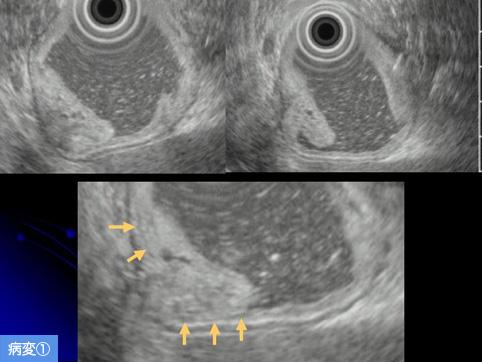

疾患(病理主体)の分類良性上皮性腫瘍/腺腫

部位(臓器別)胃(部位)/前庭

検査方法エコー

腫瘍の肉眼分類0型(表在型)/IIa型(IIa)

病変の最大径(ミリ)20〜24

多発腫瘍(同一臓器)有(同時性)